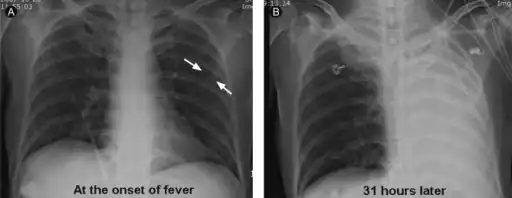

It is a common misconception and pure speculation that atelectasis causes fever. A study of 100 post-op patients followed with serial chest X-rays and temperature measurements showed that the incidence of fever decreased as the incidence of atelectasis increased.[4] A recent review article summarizing the available published evidence on the association between atelectasis and post-op fever concluded that there is no clinical evidence supporting this speculation.[5]